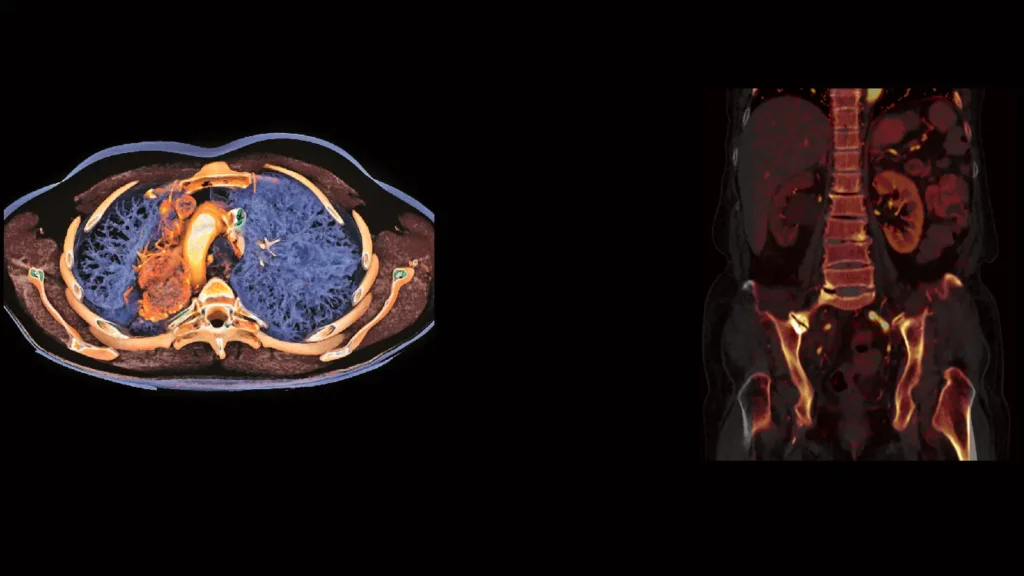

Oncological surgical planning Tumor measurement Volumetric assessment 3D Volumetric quantification PET Metabolic assessment Followup imaging and assessment after Immunotherapy

Tumor volume measurement 3D cardiac/coronary analysis 3D body imaging 3D musculoskeletal imaging 3D breast imaging 3D nuclear medicine and PET